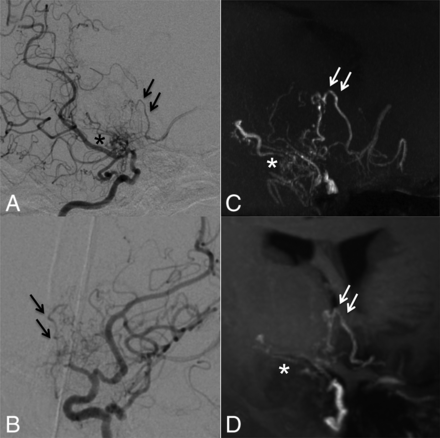

Case 8. Selective right internal carotid angiography (anteroposterior, A; right 45°oblique view, B) shows anastomosis between the posterior communicating artery and the thalamostriate arteries (arrows, type c). MIP from TOF-MRA (C) demonstrates this anastomosis clearly as well as connection with the anterior choroidal artery (asterisk). The latter anastomosis could neither be detected in DSA nor visualized by MIP from MPRAGE (D).

Case 5. Selective right internal carotid angiography (right 45° oblique, A; left 45° oblique view, B) shows intrastriatal anastomoses among thalamostriate arteries running through the periventricular space (arrows, type d). MIP from TOF-MRA (C) excellently demonstrates these networks as well as focal connections among Moyamoya vessels in the basal cistern (asterisk, type f). MIP from MPRAGE (D) moderately depicts the network; however, basal Moyamoya vessels are poorly visualized.